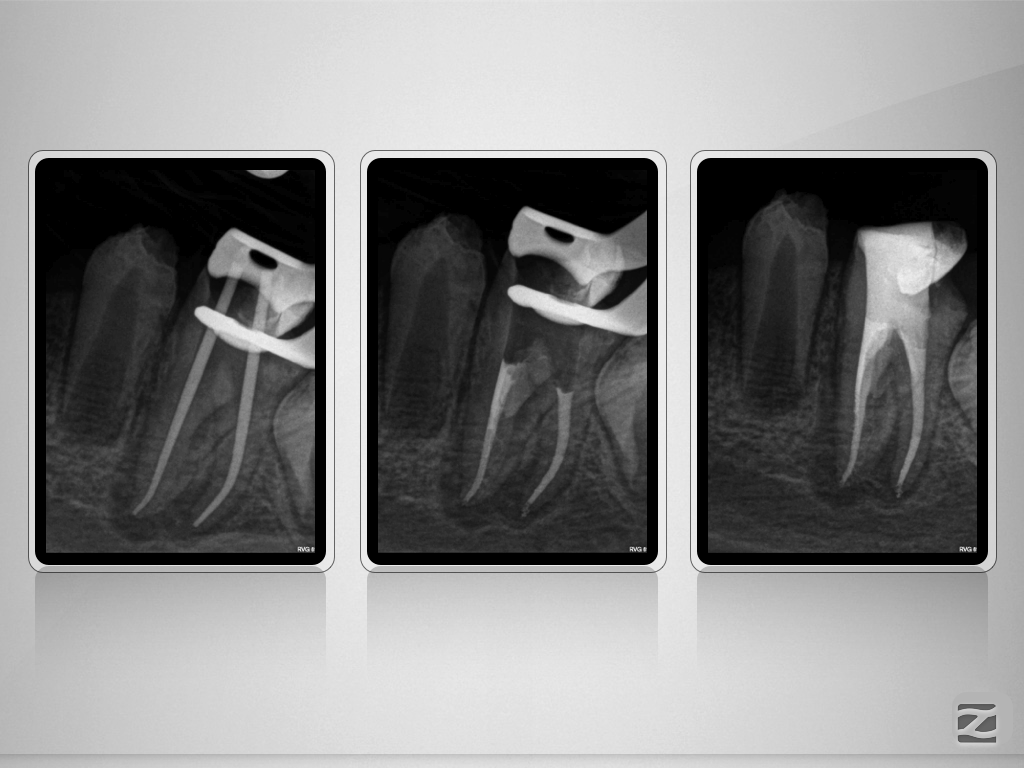

36D.009

Doppeltes C